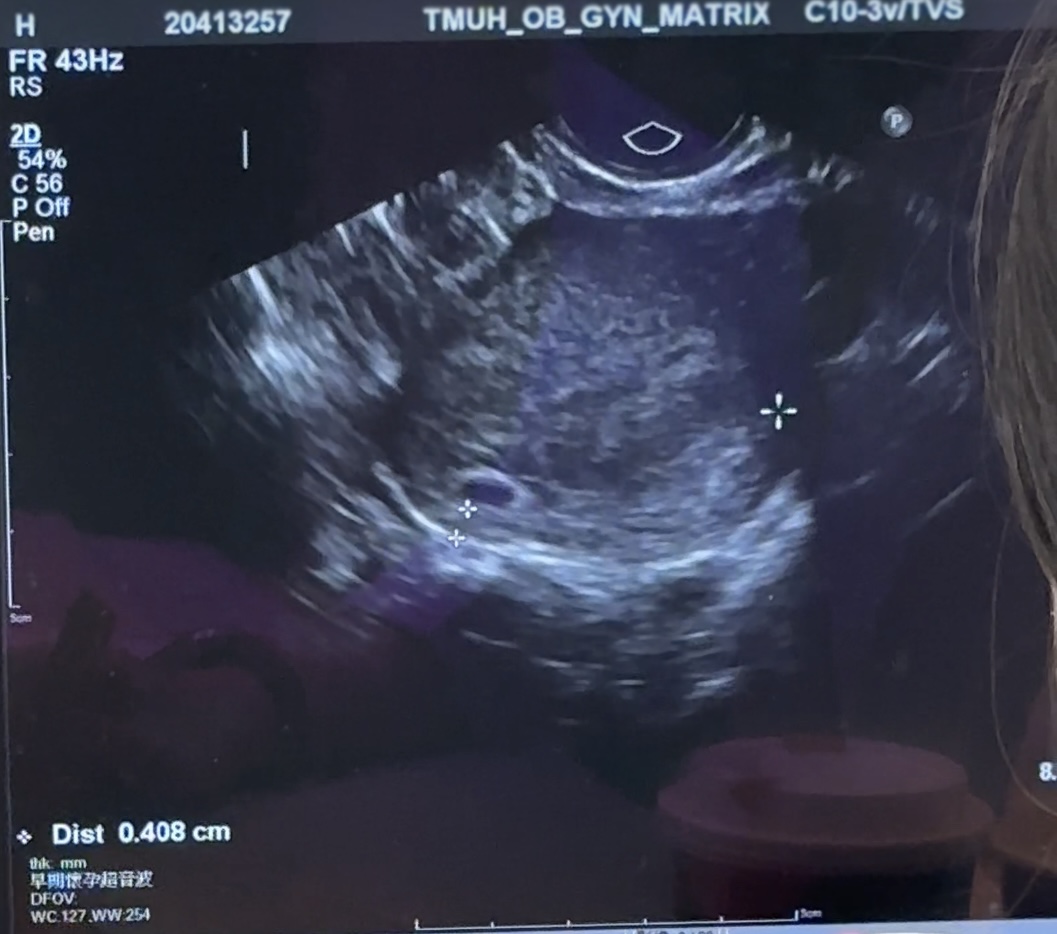

بچه ها این سونوی منه. طبق آخرین پریودم الان ۷ هفته و ۳ روزمه بر اساس سونو نمیدونم. کیسه زرده و ساک بود اما جنین نه.

دکتر بهم گفت ساک نزدیک دهانه رحمه و خیلی پایینه اگه نیاد بالا باید سقط بشه😭😭😭😭😭😭

واژینال رفتم، نمیدونم گفت نزدیک دهانه رحمه و اگه همینجا رشد کنه خطرناکه بعد بتامم آهسته میره بالا

کفت یه هفته دیره دوشنبه بیا که اگه همونجوری بود زود دفعش کنی... داغون شدم...